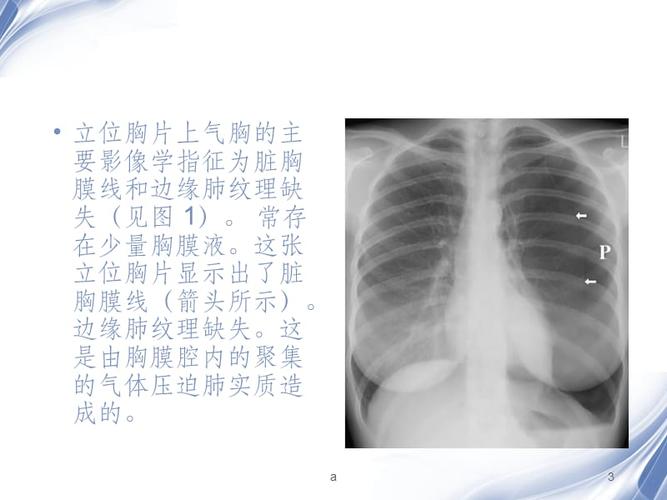

气胸x线胸片图解胸廓,气胸x线胸片图解x光片

气胸患者胸部x线表现

从胸片及ct检查常用于诊断气胸,胸片儿简单便捷.

气胸的x线表现,6个病例帮你搞定